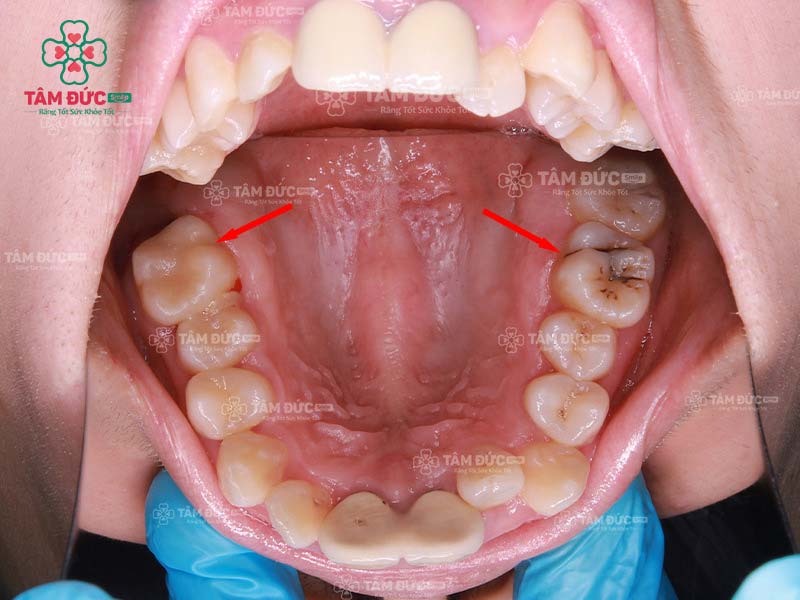

Răng số 6 bị sâu chỉ còn lại chân răng thì có niềng được không?